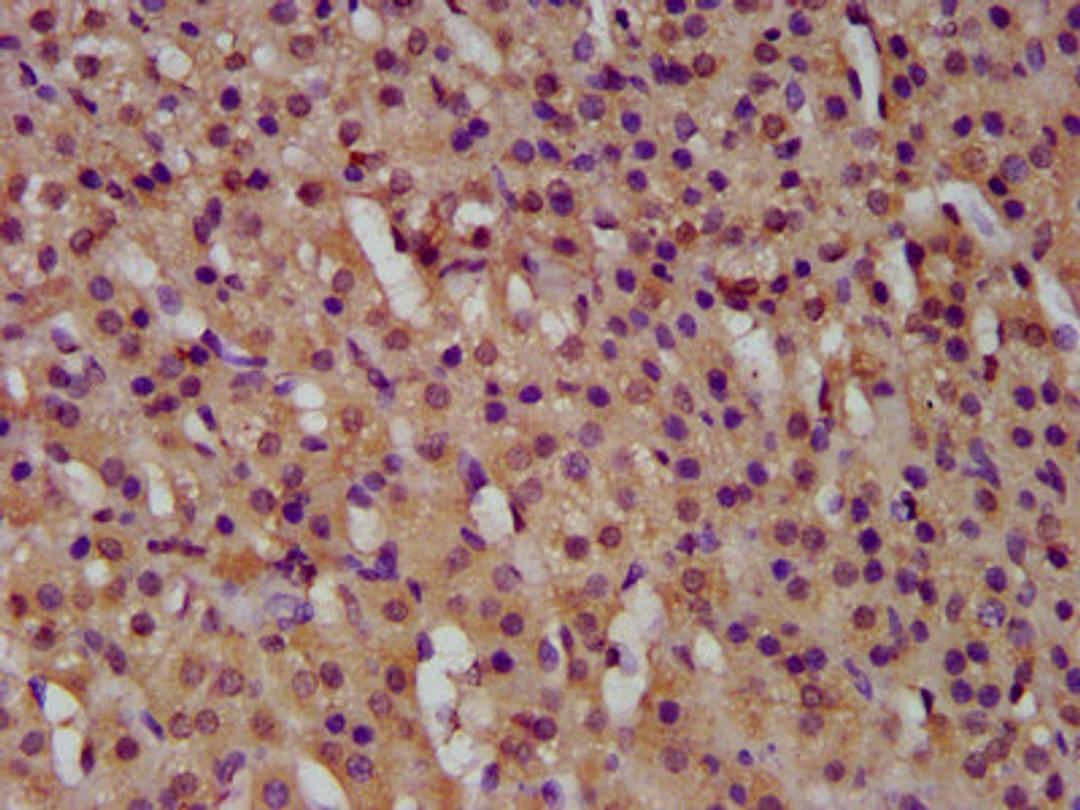

IHC image of CSB-PA010031LA01HU diluted at 1:500 and staining in paraffin-embedded human adrenal gland tissue performed on a Leica BondTM system. After dewaxing and hydration, antigen retrieval was mediated by high pressure in a citrate buffer (pH 6.0). Section was blocked with 10% normal goat serum 30min at RT. Then primary antibody (1% BSA) was incubated at 4°C overnight. The primary is detected by a biotinylated secondary antibody and visualized using an HRP conjugated SP system.